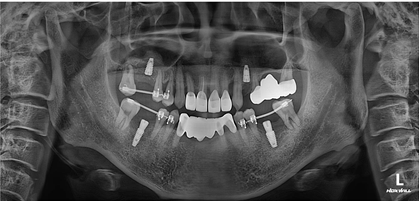

임플란트 4개로 마무리 되었습니다.

쓰러진 치아들도 제자리오 잘 세워졌습니다.

이렇게 치료하면 내치아를 최대한 살릴 수 있습니다.

더불어 임플란트 치료 갯수도 줄어드니까

비용적으로도 유리합니다.